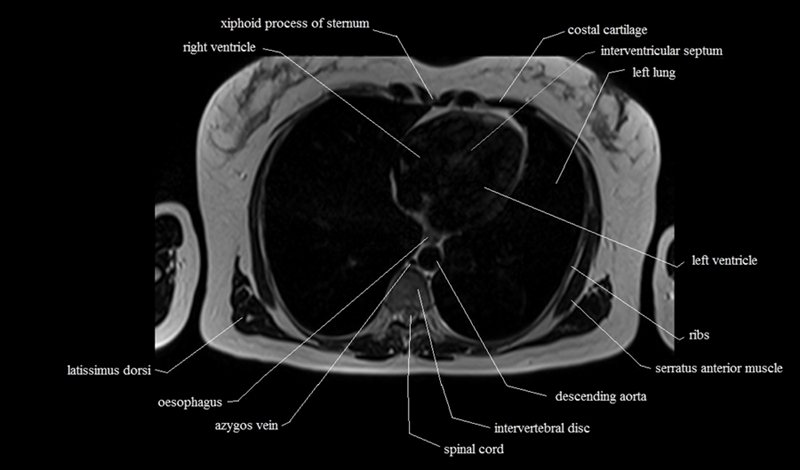

MRI Axial Cross Sectional Anatomy of Chest

This MRI chest (thorax) axial cross sectional anatomy tool is absolutely free to use. Use the mouse scroll wheel to move the images up and down, or alternatively, use the tiny arrows (→) on both sides of the image to navigate through the images. For a more detailed view, double-click the image to view it in full screen, and use the menu in the top right-hand corner to view individual slides or play them in a loop.